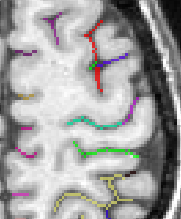

Each fold includes several buckets of voxels corresponding to the topologically simple surface making up its core (GREEN), its bottom lines (including branche's bottoms) (RED) and a few additional voxels corresponding to small or spurious branches (CYAN). Here is the example of a central sulcus:

You can get images of the bottom, of the simple surface or the sum of everything. You can also get the junction between each sulcus and the brain hull, which corresponds to the line which is sometimes drawn manually by some teams. Anatomist's viewer show you the result (the eyes):

If you want to get only one sulcus, or a small list of sulci, write their label in the attibute "label_values". For instance "S.C._left" or "S.C._left S.F.sup._left":